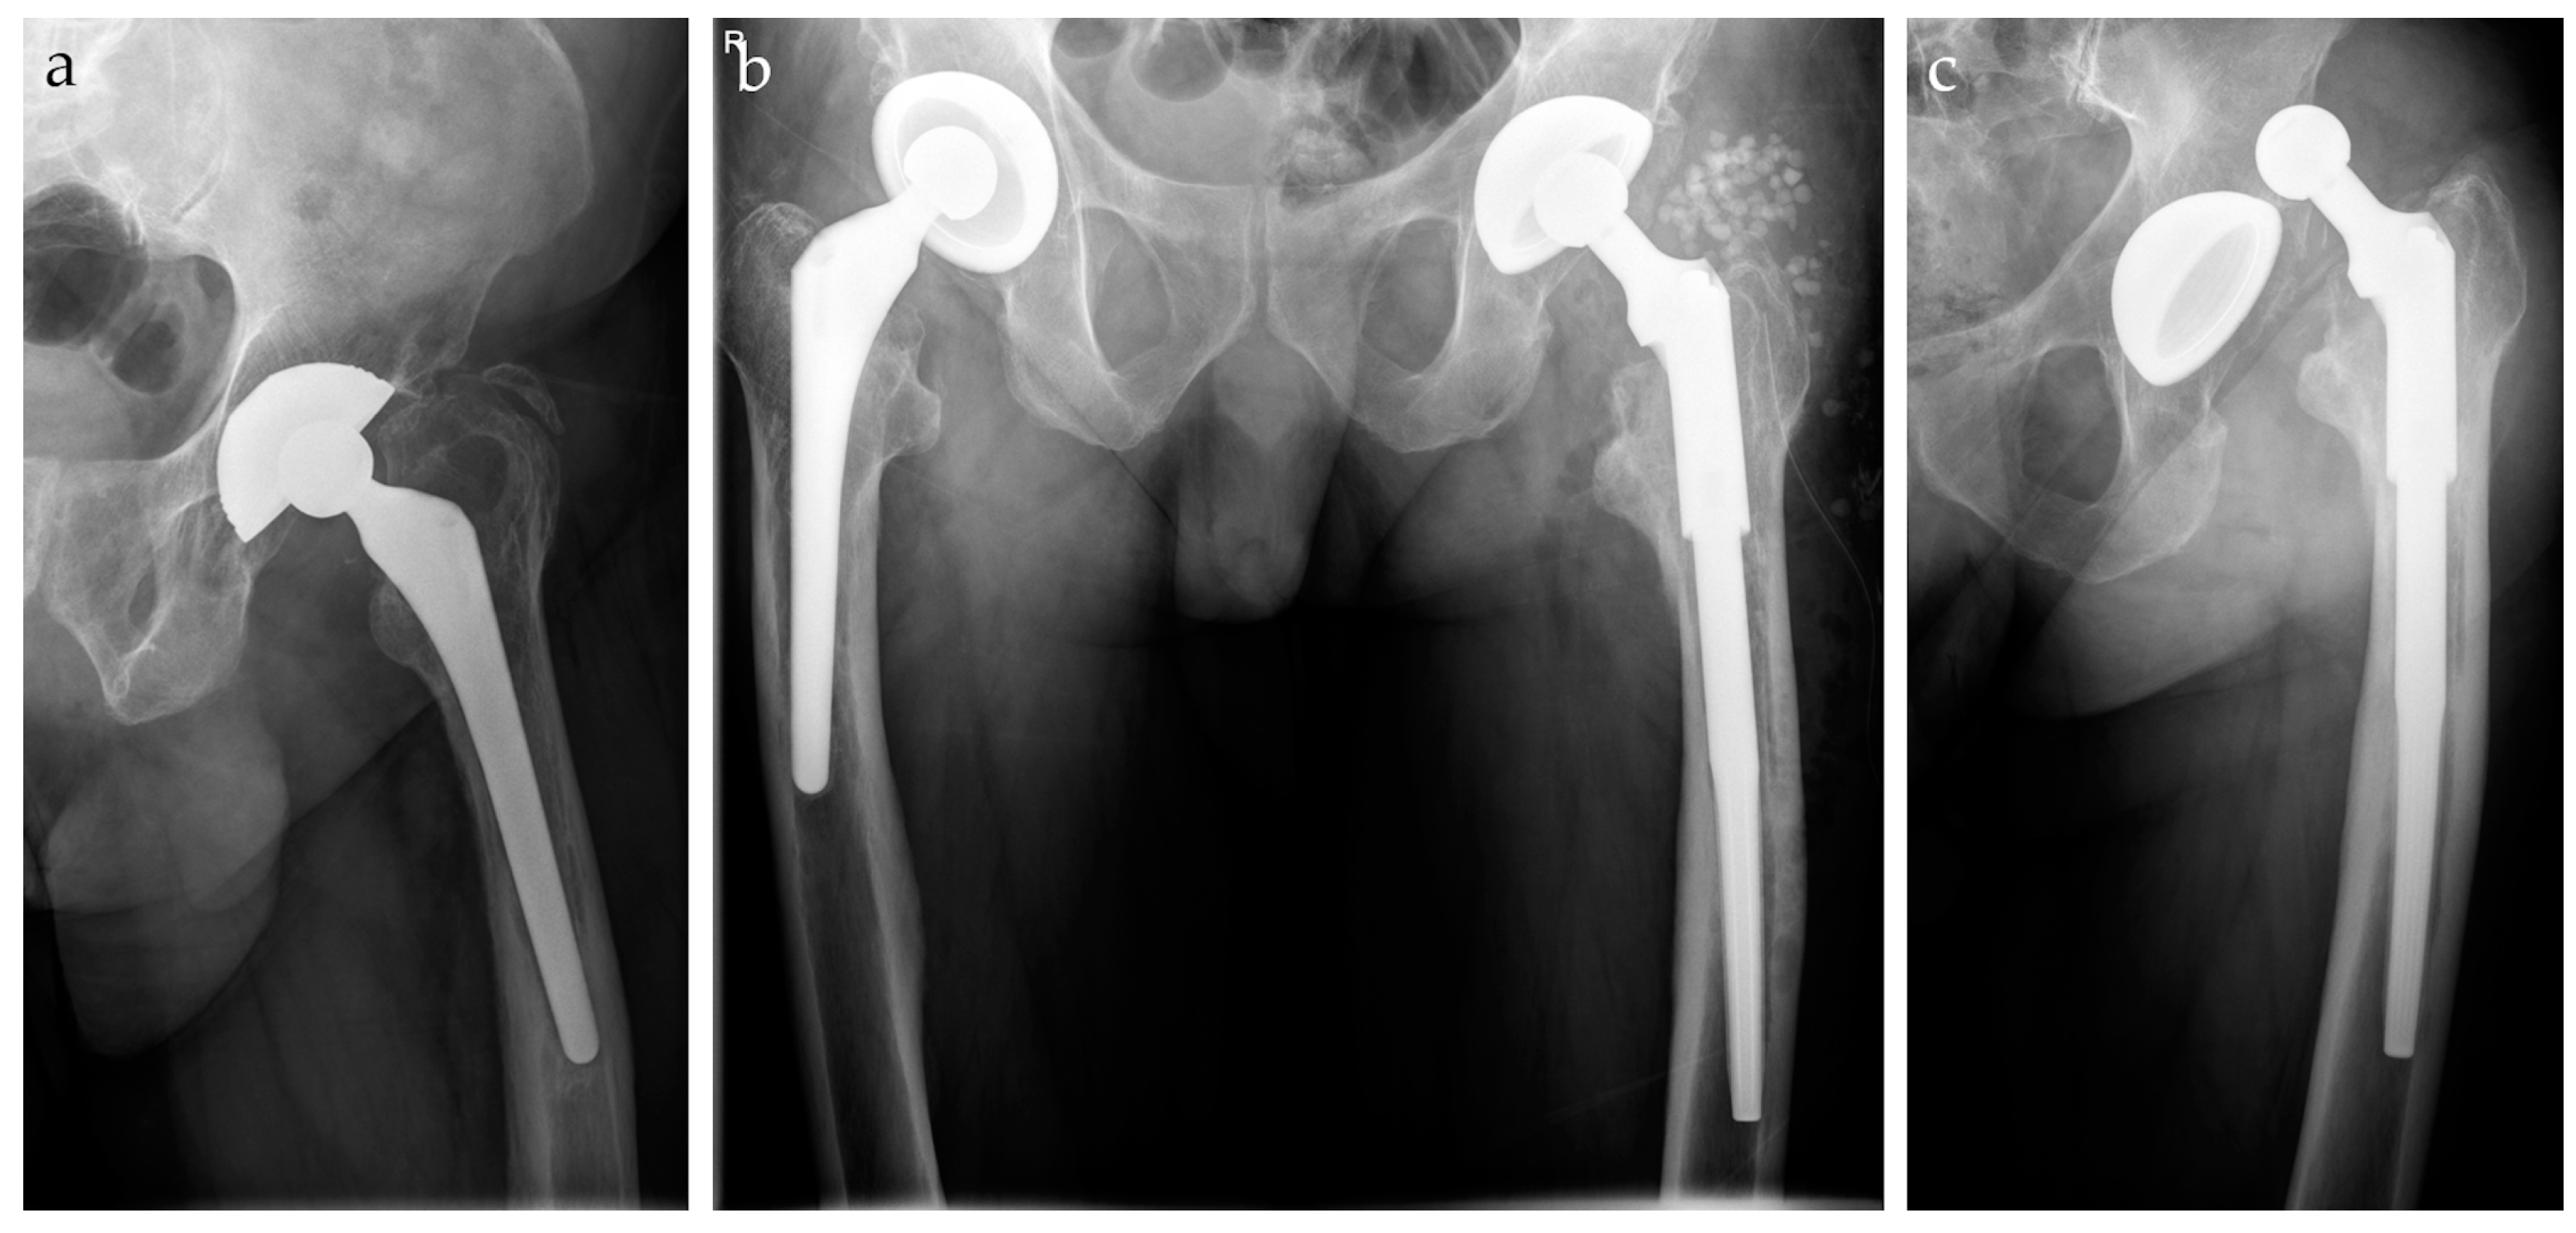

2. Materials and Methods

3.1. Periprosthetic Joint Infection

3.2. Dislocation

3.3. No Complications